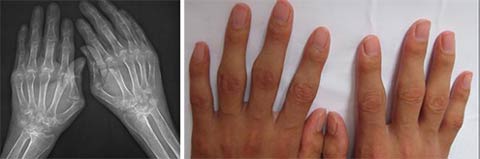

(图:治疗前,患者ct示关节肿胀、尺偏畸形)

医生会诊结果:双肘关节肿胀,关节周围压痛(+),双肘关节活动受限。双手呈尺偏畸形,2、 3、4、5手指呈鹅颈畸形。